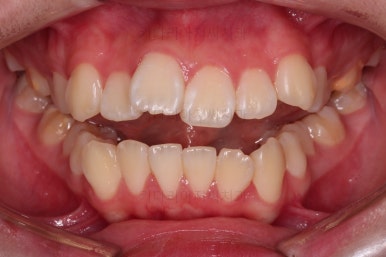

부산덧니교정 마무리를 한 모습인데요.

가지런한 모습 좋고, 교합이나 중앙선 등 매우 잘 맞네요.

전후를 비교해 볼게요.

치열, 교합, 악궁의 형태 매우 좋아졌어요.

다만 아직 어려서 카메라 사진을 찍을 때 어색해서 그런지 활짝 웃는 입술이 자연스럽진 않네요.

연습하면 충분히 좋아지고요.